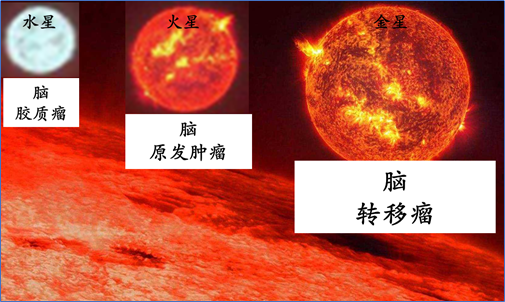

说到脑癌(脑瘤),想必大家并不陌生。但是,当被问到:哪种脑癌最多见?答案可能回出乎您的意料,它就是:脑转移瘤!脑转移瘤的发病率,甚至比原发性脑恶性肿瘤高出10倍以上!它可以发生在全身几乎所有恶性肿瘤类型,包括肝癌……

脑转移瘤发病率

肝癌及脑转移发病率:脑转移瘤以肺癌来源为最多,占比可达40%~60%,其次为乳腺癌,其它来源有胃肠道肿瘤、肾癌、妇科肿瘤、肝癌等;其中,肝癌脑转移占所有脑转移瘤的1-2%左右;另外,肝癌患者发生脑转移概率大约为0.2%~2.2%。